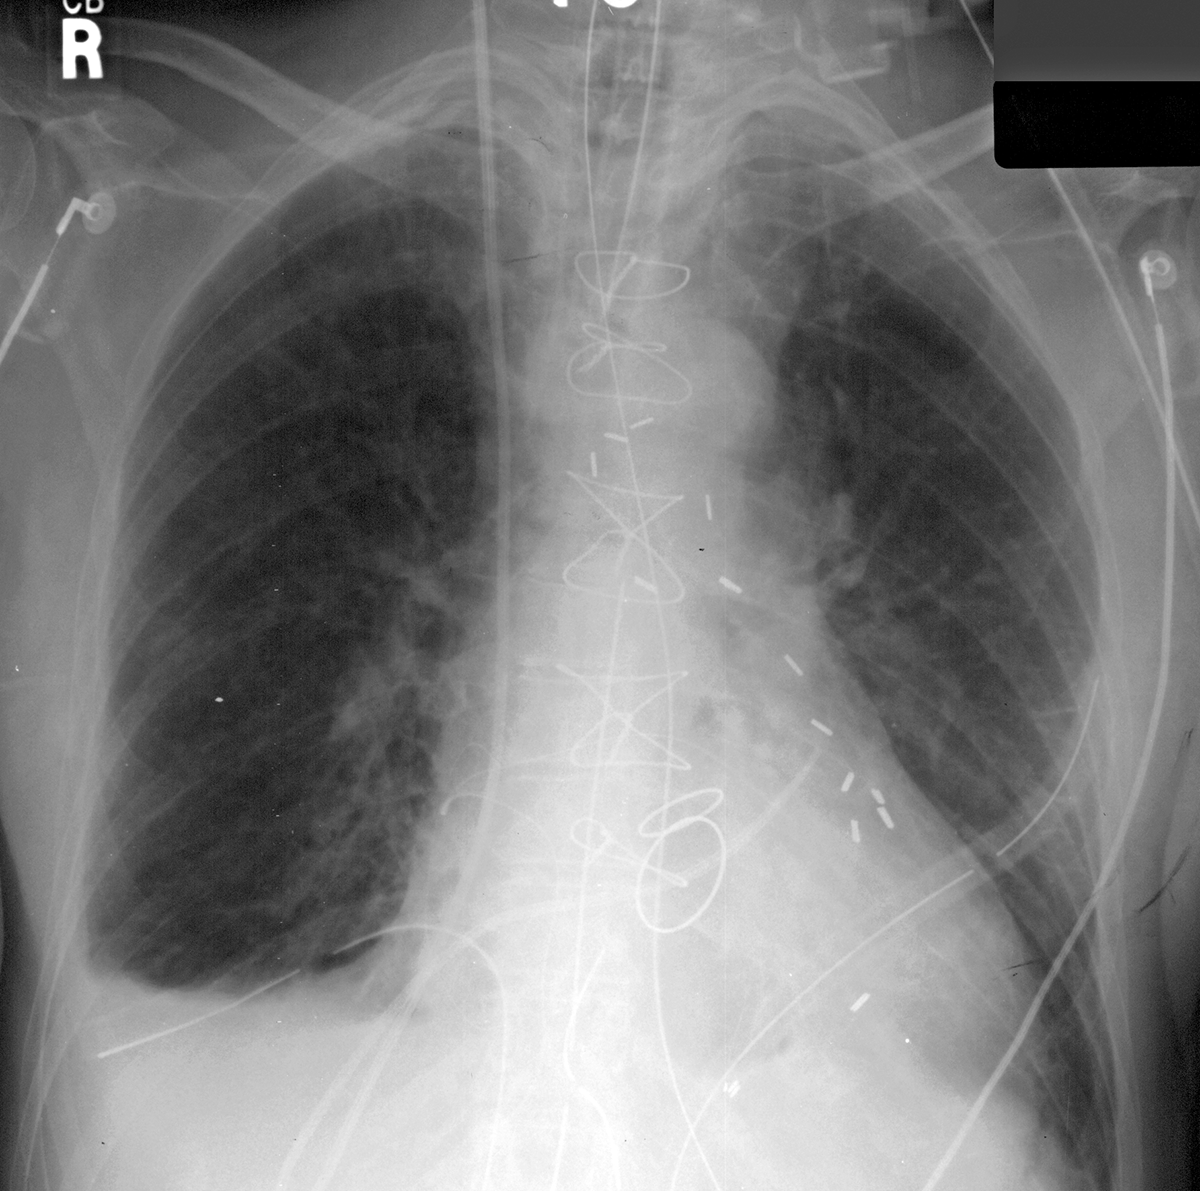

advanced case for lines and tubes